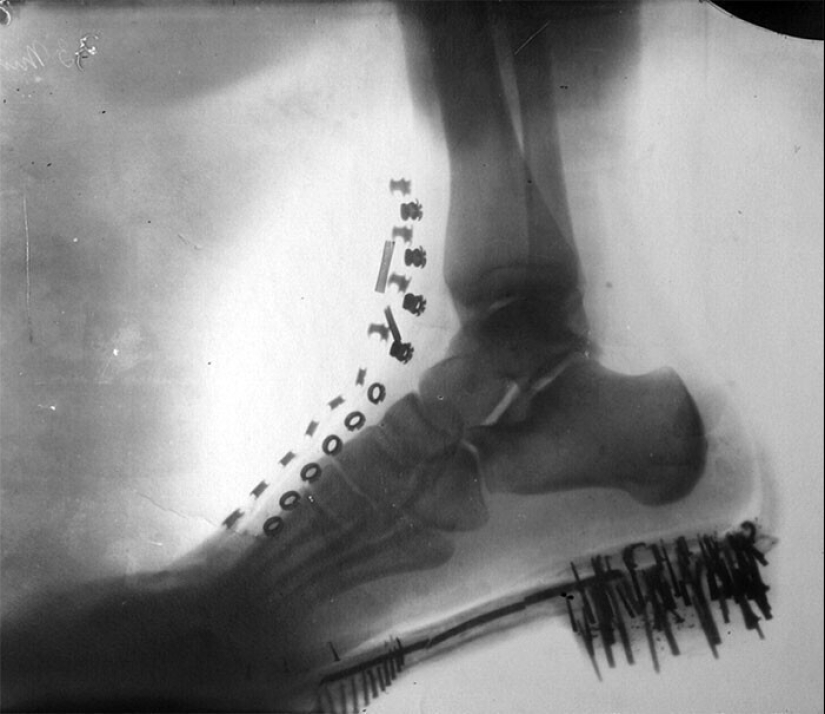

La pierna de Nikola Tesla en el Zapato: x-ray, hecho por él mismo en la cámara de su propio diseño en 1896